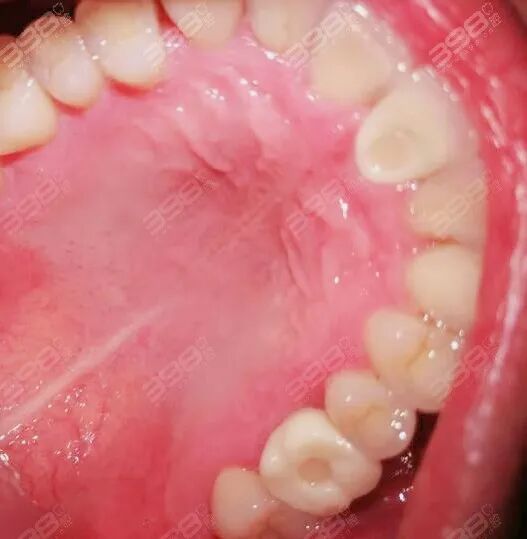

两颗种植牙,一颗在左下5,一颗在右上7,两颗都符合即拔即种,种植体选择的是诺贝尔pmc价格21000一颗,因为做两个再加上活动,所以便宜了一些,骨粉1000一盒,人工生物膜、CT忘记价格,配药免费。诺贝尔虽然贵但是稳定性很不错的,增加骨结合的速度,能与人体相融,所以年轻人,牙槽骨不好的人都可以选择这个。

种牙大概流程:术前吃饭补充体力、然后吃药抽血(抽血好像做人生物膜,有机器提取抽的血,排异反应小一些)大概40分钟左右。面部消毒,再给种植处打麻药,拔残余的烂牙桩,在切开牙骨在牙骨上打洞,放种植体缝合咬棉球止血,然后再去拍CT。其实打了麻药全程不会痛,主要是内心恐惧,能感受到切牙骨、锤牙齿、钻牙骨、缝合。

术后反应:医院给我开了六天消炎止血的药(开了2颗止痛药,不痛就不吃),从昨天中午种完牙到现在,没有疼痛,今早睡起来左脸有点点肿,不太明显,主要是左边嘴角泡了起壳了,不能张太大,但也不能吃喜欢排骨、大骨头了,看见家里人啃肉我实在太馋了,流口水还得咽下去!做种植牙简直不想活了!为什么不能让我大口吃肉!还要吃几天流食,感觉自己非常可怜,除了不能随便吃东西,其他术后反应倒是没有。